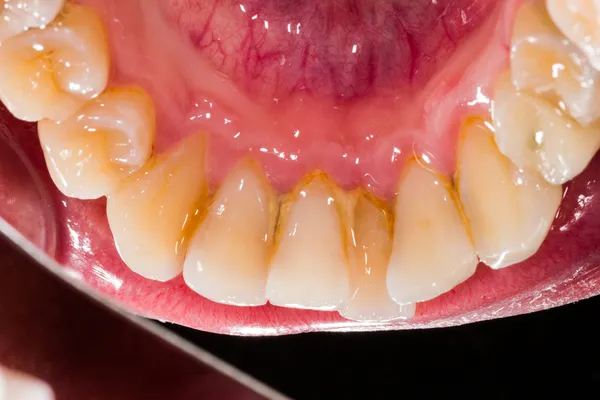

Dişetinin tartara yakın kısmındaki kılcal damarlar genişleyerek tartar içindeki bakterilere karşı savunma oluşturur. Elma ısırma, diş fırçalama gibi diş etlerinde mekanik baskı oluşturan eylemlerden sonra genişleyen kılcal damarlar travma geçirerek kanamaya başlar. Diş eti kanaması sorunu ancak neden olan tartarın çıkarılmasıyla çözülebilir. Tartar alındıktan sonra kılcal damarlar daralır, ödemli ve kırmızı görünüm kaybolur ve diş eti eski sağlıklı pembe görünümüne geri döner.

Diş eti kanamalarının ihmal edilmemesi gerekir. Eğer bunun sonrasında bakımı tekrar düzenli bir şekilde yapıp diş ve diş eti üzerindeki plak dediğimiz besin artıklarının, mikro seviyede öğütülmüş olan ve dişlerin üzerinde biriken kısımları uzaklaştırırsak tekrar sağlıklı hale dönebiliriz. Fakat biz eğer bu aşamada diş bakımını düzenli ve olması gereken biçimde yapmamışsak bir ileri aşamasında diş etinin üzerindeki yüzeysel kanamalar ve iltihaplar oluşmaya başlar. Bu aşamada diş hekimine giderek daha profesyonel bir temizlik yaptırmak zorundayız.